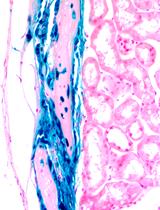

The goal of this protocol is to establish a procedure for cultivating stem cells on a fibrin carrier to allow for eventual transplantation to the eye. The ability to transfer stem cells to a patient is critical for treatment for a variety of disorders and wound repair. We took hair follicle stem cells from the vibrissae of transgenic mice expressing a dual reporter gene under the control of the Tet-on system and the keratin 12 promoter (Meyer-Blazejewska et al., 2011). A clonal growth assay was performed to enrich for stem cells. Once holoclones formed they were transferred onto a fibrin carrier and cultivated to obtain a confluent epithelial cell layer. Limbal stem cell deficient (LSCD) mice were used as the transplant recipient in order to test for successful grafting and eventual differentiation into a corneal epithelial phenotype.

Stem cells are widely used as a therapeutic tool, thus a means for delivery is essential. In fact, many researchers and companies are searching for the best way to deliver cells into the human body to optimize cell survival as well as integration into the host tissue. Injection methods have been widely used in animal models but often result in poor survival and integration. Techniques utilizing biomaterials and surgical devices are currently being employed. One technique that has been utilized to deliver stem cells is fibrin carriers. Fibrin gel is a degradable biopolymer that can adhere to native tissue allowing for cell attachment, migration and proliferation (Ehrbar et al., 2005). Fibrin gels have many advantages including biocompatibility, controlled degradation (Kjaergard et al., 1994; Sidelmann et al., 2000), uniform cell distribution and high cell seeding efficiency (Swartz et al., 2005). Fibrin gels have been utilized for treating skin burns (Pellegrini et al., 1999; Ronfard et al., 2000), junctional epidermolysis bullosa (Hirsch et al., 2017) and corneal damage (Pellegrini et al., 1997; Rama et al., 2010). The method described here uses a fibrin carrier to transplant hair follicle derived stem cells onto the ocular surface of a limbal stem cell-deficient mouse. Cell engraftment and differentiation was assessed for a 5-week period via fluorescent microscopy.